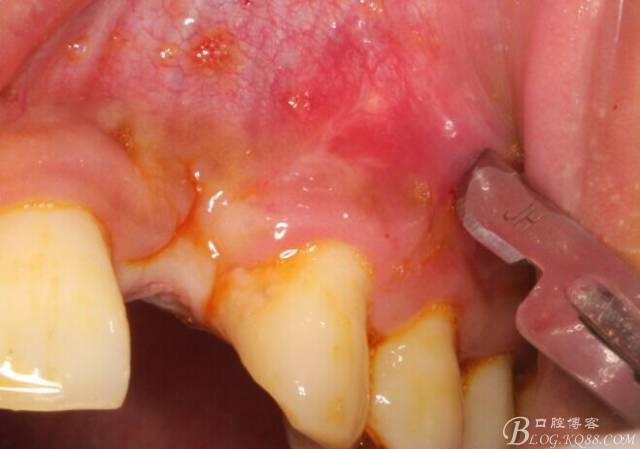

10天拆線一切正常,又過了兩周患者復(fù)診,自述期間無異常??趦?nèi)檢查,真的嚇了一跳,唇側(cè)鼓了個包,擠壓有白色分泌物溢出,絕對不是膿液,液體排除后,術(shù)區(qū)觸診空虛,外觀塌陷。這時候考研大夫的時刻到了,是先觀察一段時間再說?還是馬上進行處理?我的回答是:馬上處理!如果你沒有及時處理,而是放患者回家觀察,那么接下來會發(fā)生如下情況:1.回家后患者家屬及親友會有很多你可以想象得到的討論;2.患者及家屬會對你產(chǎn)生不信任,勢必會到其他門診或醫(yī)院檢查,他院大夫會不會發(fā)表對你不利的言論;3甚至?xí)蚁嚓P(guān)法律界人士找你討要說法。

于是我果斷告知患者,手術(shù)失敗了,不能拖延,如不及時處理,炎癥繼續(xù)發(fā)展會很快波及鄰牙牙槽骨?;颊呓邮芪业慕ㄗh。切開翻瓣,骨粉及生物膜消失了,骨吸收嚴(yán)重,幸運的是,因為處理及時,鄰牙骨支持依然存在。